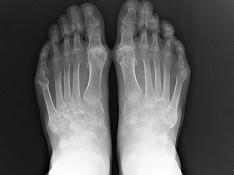

问题 男,72岁,手足多个小关节红肿热痛,并压痛明显,化验:白细胞升高,血沉增快,血尿酸升高,请结合所提供图像,选择最佳选项 ( )

选项 A、假痛风 B、滑膜炎 C、退行性骨关节病 D、痛风性关节炎 E、类风湿关节炎

答案 D